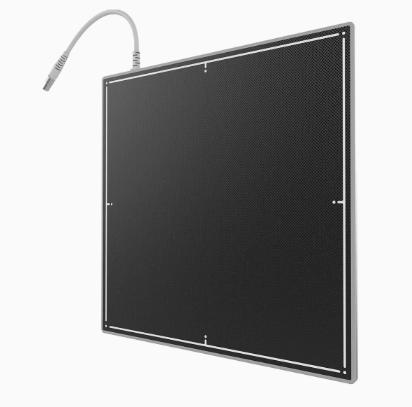

FLAT PANEL 17X17 MODELO MSL1127

Imágenes más fáciles Detectores de rayos X digitales de alto rendimiento diseñados para un uso sencillo y un transporte seguro. El mango magnético proporciona una portabilidad cómoda y se puede plegar en el panel para una rápida compatibilidad con las bandejas bucky estándar.

Construcción duradera para un rendimiento estable a largo plazo. El DEA flexible permite utilizar tecnología de diagnóstico avanzada con todo tipo de sistemas de rayos X.

Cristales de yoduro de cesio cultivados internamente y envasados herméticamente. Atención de dosis bajas más eficiente con tecnología de imagen patentada.

Panel TFT/PD de 140 µm de nuevo diseño. Un equilibrio preciso de factores de ingeniería, creado para obtener imágenes altamente detalladas.